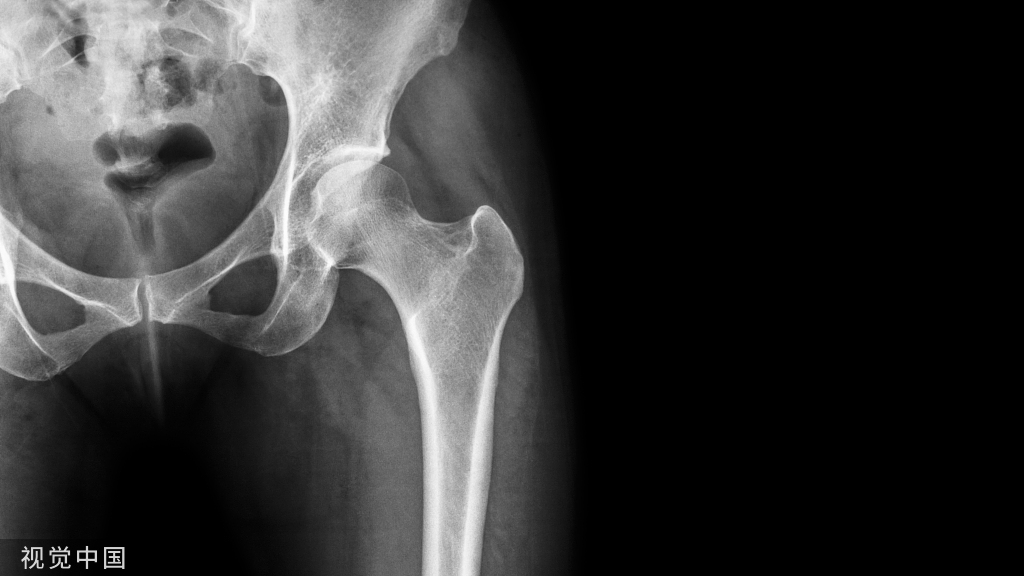

修复有骨关节、肌腱、重要脏器、大血管和神经干裸露,且无法利用周围皮肤直接缝合 封闭的创面。